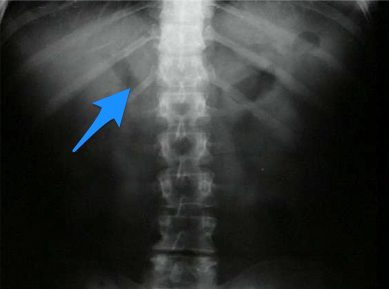

What sign is this?

Rigler sign, air on the inside and outside of the body, indicating pneumoperitoneum.